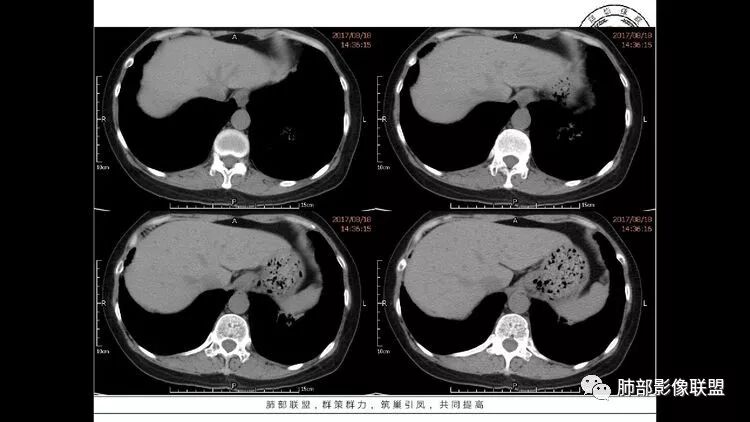

老年女性,眼炎入院,血常规正常,双肺多发囊状影,病变随机分布,形态单一,与血管关系密切,考虑LIP。左下肺混合GGO,边界尚清,贴近囊腔,鉴别腺癌。炎症指标无异常暂不考虑感染性病变。

胸CT:1.双肺多发囊性变,以中下肺为主,病变边缘可见肺动脉,部分囊内可见分隔及肺动脉,双下部分肺野周围可见小叶中心结节及树丫征。

2 左肺上叶尖后段 右肺上叶前段 右肺下叶外基底段 结节影,边界清楚,可见柔软毛刺,左肺下叶后基底段混合密度影。

3.纵隔淋巴结肿大?,以主动脉弓为界向上向下增大。

考虑:淋巴瘤肺浸润,眼部症状考虑与此有关;LIP?;继续鉴别肺腺癌?血管炎?。